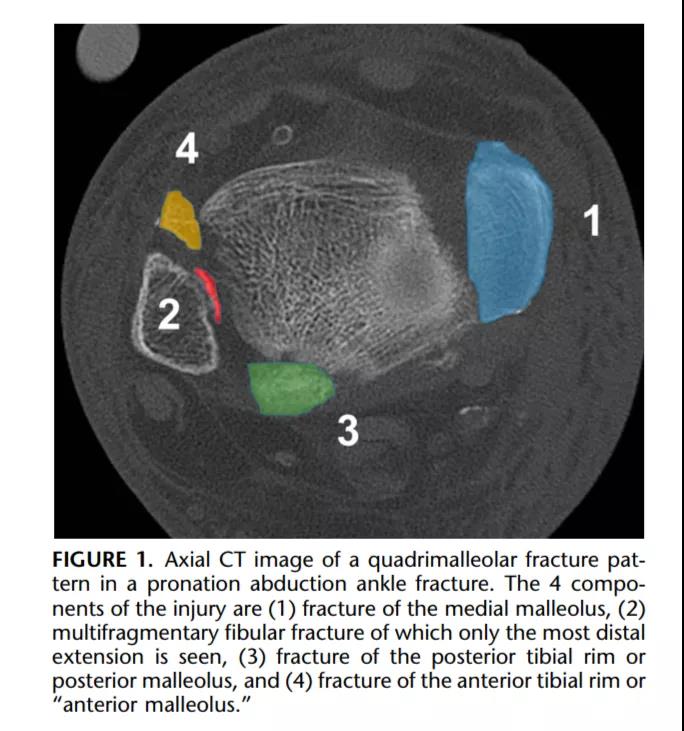

① 四踝骨折示意图:1.内踝;2.外踝;3.后踝;4.胫骨前结节(前踝)。

② 四踝骨折典型病例图。